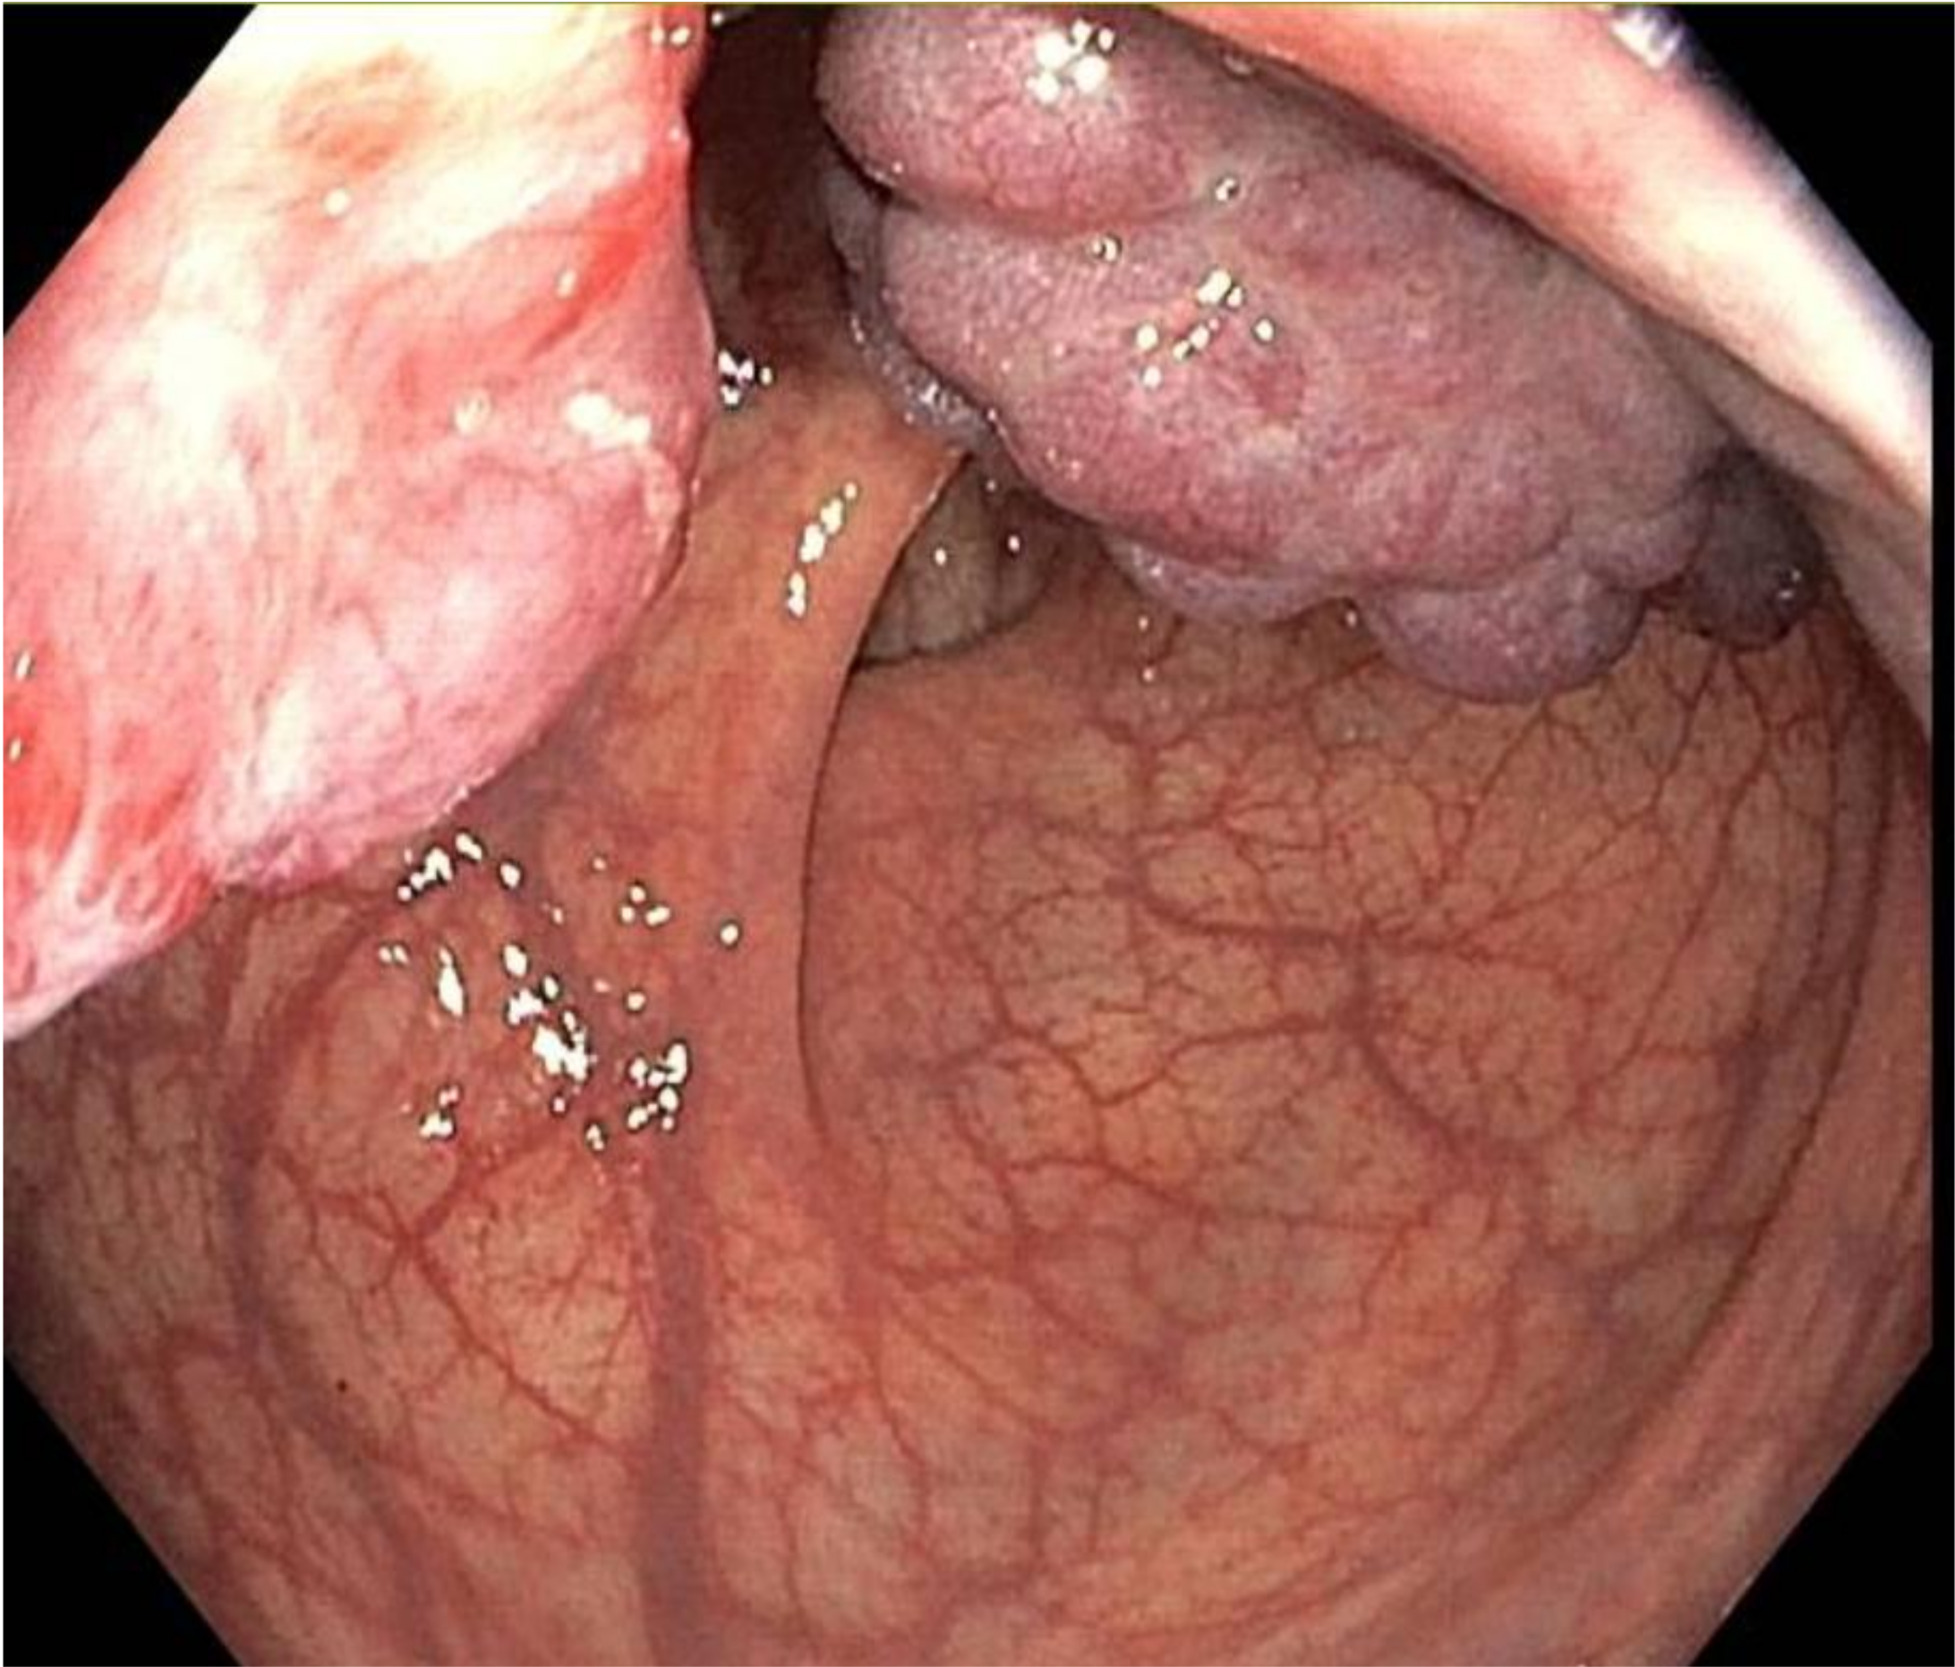

Inhomogeneous signal hyperintensity in T2-weighted sequences with a fluid/fluid level appearance, isointensity signal in T1-weighted sequences, no signal reduction in T1-weighted sequences in opposition of phase in agreement with the absence of a lipid component, no signs of signal restriction in diffusion (ADC 1.6), thin peripheral contrast enhancement, and thin septa in the structure were all features of the MRI. The lesion on the right posterolateral side appeared to affect the muscular coat, extending to the serosa raising suspicion for a teratomatous-type lesion. Following multidisciplinary consultation, surgical excision was planned. A transanal local excision was performed under general anesthesia (Figure 3). The patient’s postoperative course was uneventful, and he was discharged on the first postoperative day. Histopathological analysis revealed an edematous, ulcerated, and chronically inflamed segment of the large intestinal wall, containing lymphatic and intraparietal blood vessel ectasias consistent with hemolymphangioma. No postoperative complications were observed. The patient underwent regular follow-up evaluations, including proctological examinations, CT scans, and MRI studies (Figure 4) every six months for the initial two years, followed by annual assessments. At four years postoperatively, there is no evidence of disease recurrence.